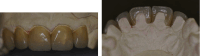

With the development of ceramic technology, prosthodontic ceramics are becoming a useful option for improving esthetic outcomes in dentistry. In this paper, various ceramic materials were reviewed and evaluated, and their advantages and disadvantages and indications in oral prosthodontics were analyzed objectively. The properties of resin-based ceramics, polycrystalline ceramics, and silicate ceramics were compared and analyzed. Resin-based ceramics may replace other ceramic materials in the CAD/CAM field.